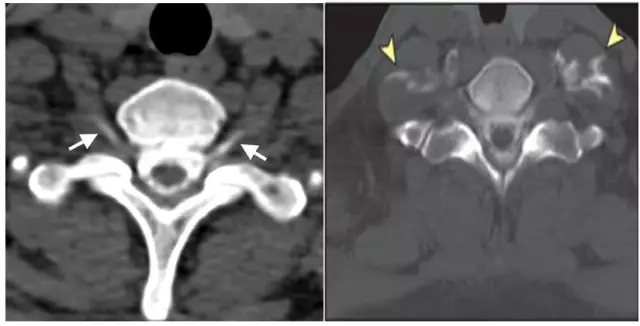

腰穿检查可以明确低颅压诊断,有时因颅内压力过低,可导致腰穿失败。为寻找瘘口,通常采用CT全脊髓造影(图13)或MRI全脊髓造影,当腰穿失败时,可采用磁共振脊髓水成像替代。硬膜外血贴治疗目前被认为是治疗自发性低颅压最有效的方法。

图13. CT脊髓造影能够明确脑脊液漏的部位和漏点数量。